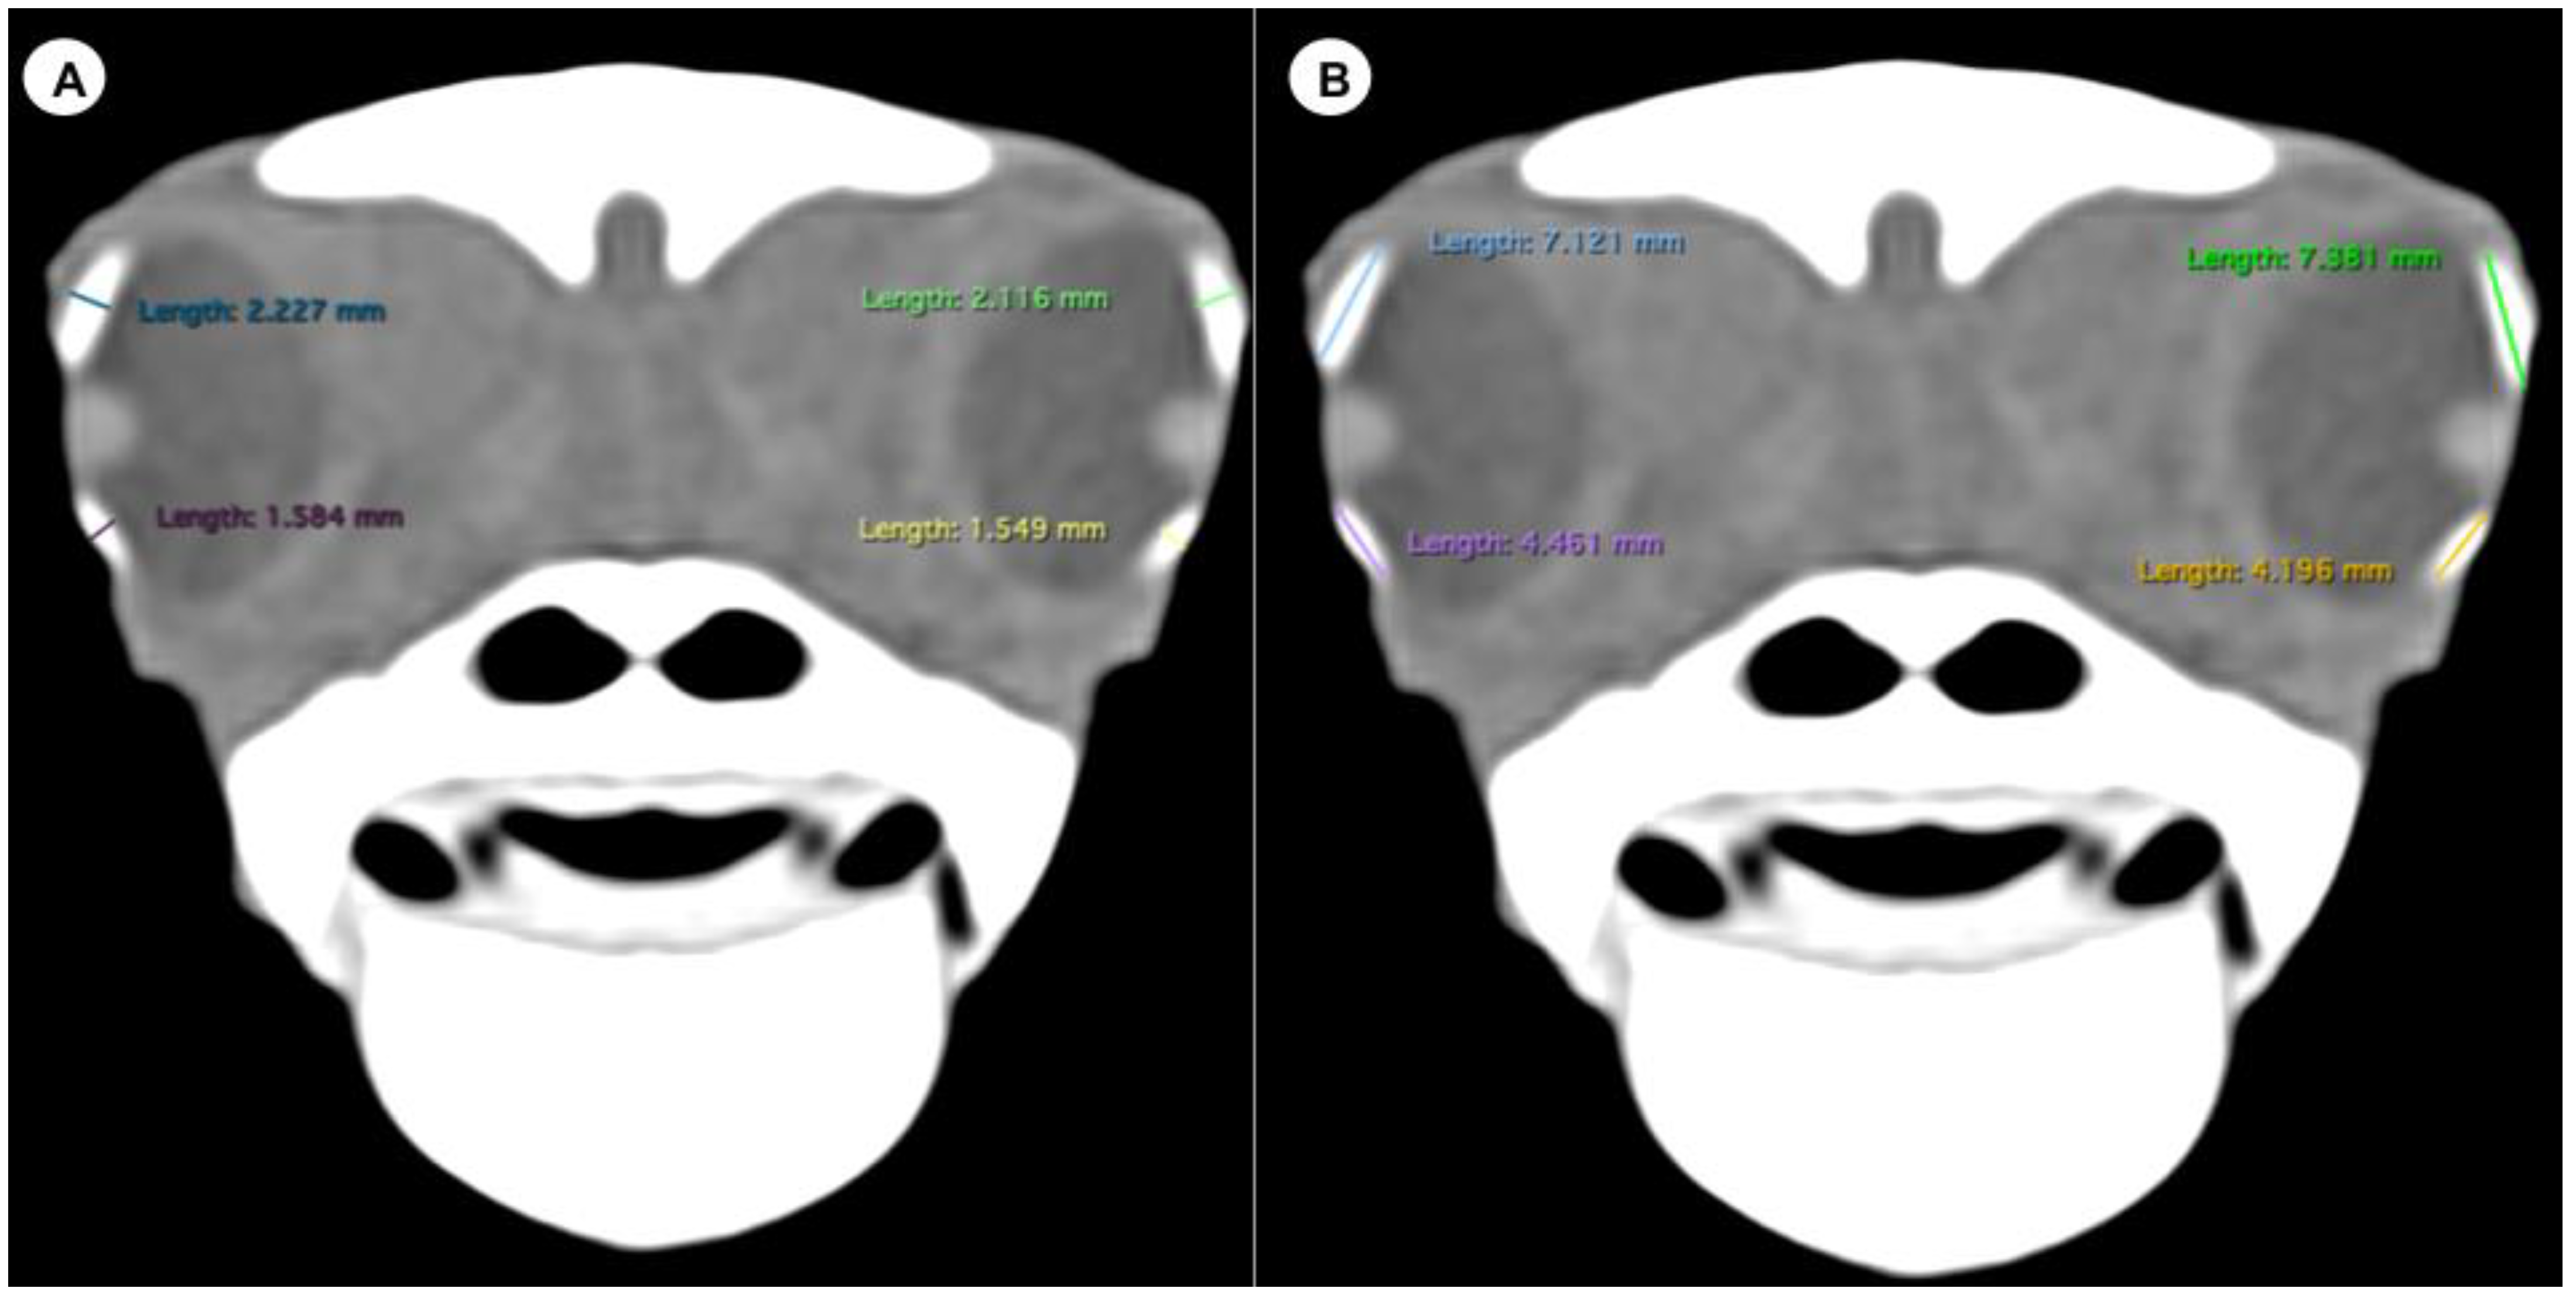

- (A)

- Transverse plane respect to the eyeball

- Lens diameter, understood as the maximum distance between the lateral and medial edges of the lens (equatorial diameter) (Figure 1A).

- Internal diameter of the sclerotic ring, or maximum distance between the inner lateromedial edges of the ring, close to the cornea (Figure 1A).

- External diameter of the sclerotic ring or maximum distance between the outer lateromedial edges of the ring, close to the sclera (Figure 1A).